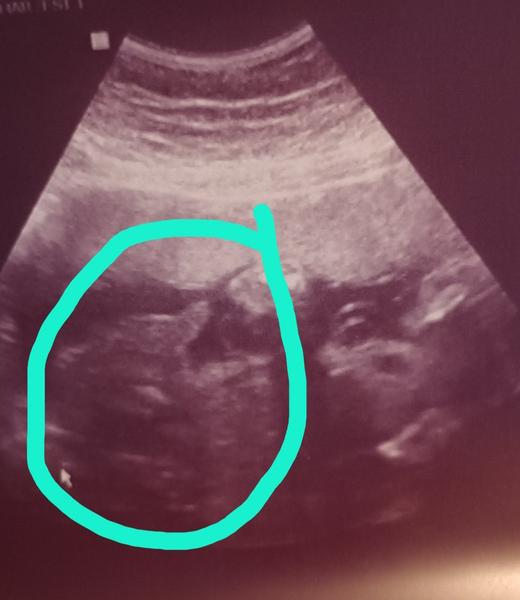

@ematomasova mám doma dvě holky a vypadá to podobné. Dovolila jsem si " kávové zrno" označit.

@sebestka Myslela jsem si to taktéž 😀 děkuji za Vaši odpověď. Na velkém ultrazvuku mi sdělili holku a poté na gynekologii kluka. Byla jsem z toho zmatená 😀 takže budu určitě věřit velkému ultrazvuku

@ematomasova Ano, ano. Měla jsem to u druhé dcery stejně. Na velkém ultrazvuku holka, gynekolog tvrdil kluka a narodila se holka.

@ematomasova mám to teď stejně. Na velkém utz mi řekli holku a na gynekologii kluka. Rodim až v cervenci, ale vidím to spíš na toho kluka. Aspoň bude mít syn parťáka 😁